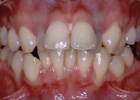

歯を抜いて治療した例 その1

治療前

治療途中

治療後